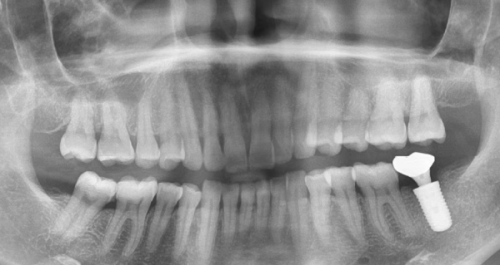

X线检查也是重要的一环。它能帮助医生清晰地看到牙槽骨的形态、密度等信息,从而正确地确定种植体的植入位置和深度。就像盖房子需要严谨的地基图纸一样,X线检查为种植牙手术提供了重要的参考依据。

接下来,医生会在牙槽骨上钻一个小孔。这个小孔的大小和深度都是经过严谨计算的,以确保种植体能够正确地植入。然后,医生会将由钛或其他金属材料制成的种植体放入这个小孔内。钛这种材料具有良好的生物相容性,能够与牙槽骨良好地结合在一起。就像给牙齿找到了一个坚固的“家”,种植体会为未来的牙齿提供稳定的支撑。

在愈合期间,定期到医院进行复查是非常重要的。医生会通过各种检查手段,如X线检查等,来确保种植体正常愈合。如果在复查过程中发现任何问题,医生可以及时采取措施进行处理。同时,在这个阶段,你也要注意口腔卫生,避免食用实力强的食物,给种植体一个良好的愈合环境。